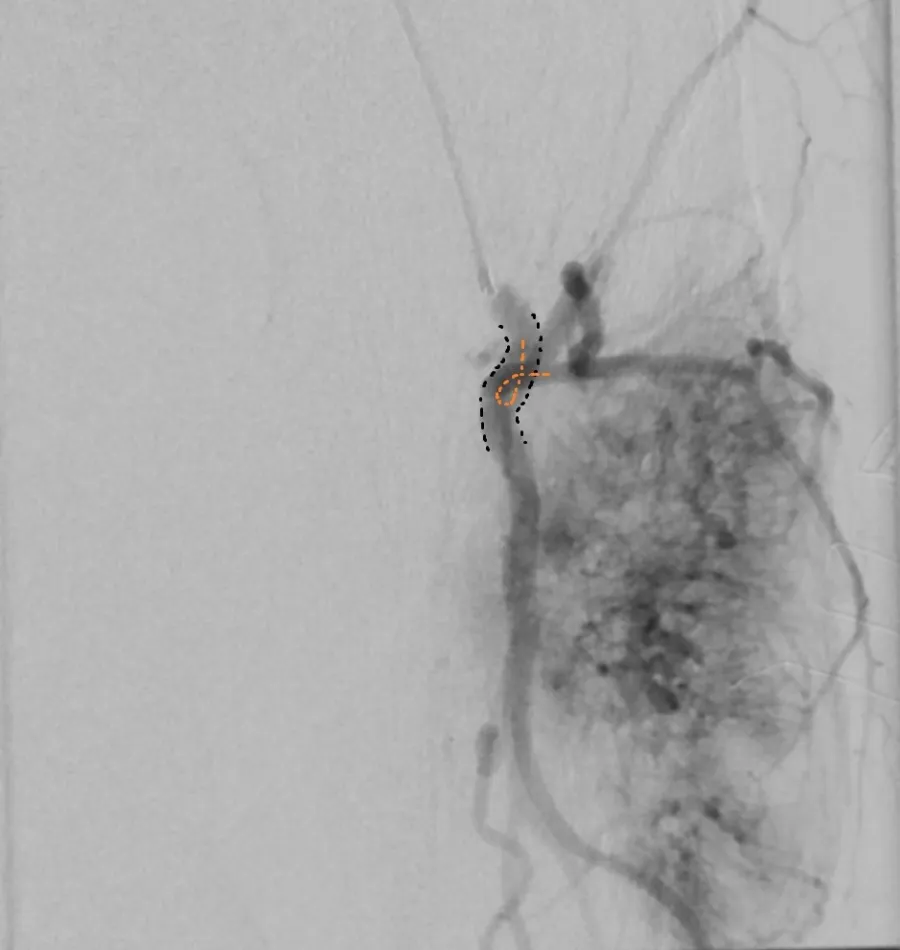

Adequate catheter position attained using the Swift Ninja Catheter by Merit Medical. Final image showing reduced vascularity.